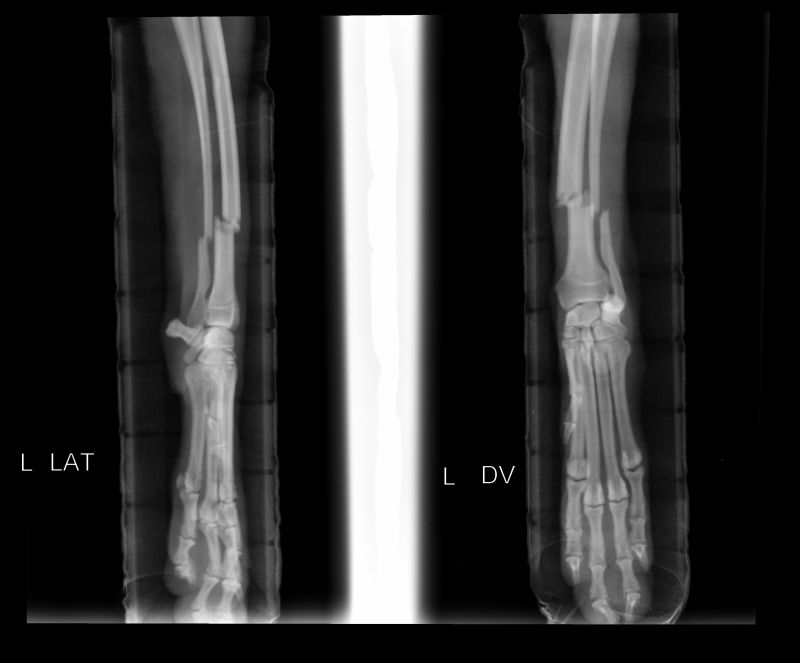

Abnormal Pathology on your pet

Shown on x-ray images which we have taken over the years.

Some interesting patient cases